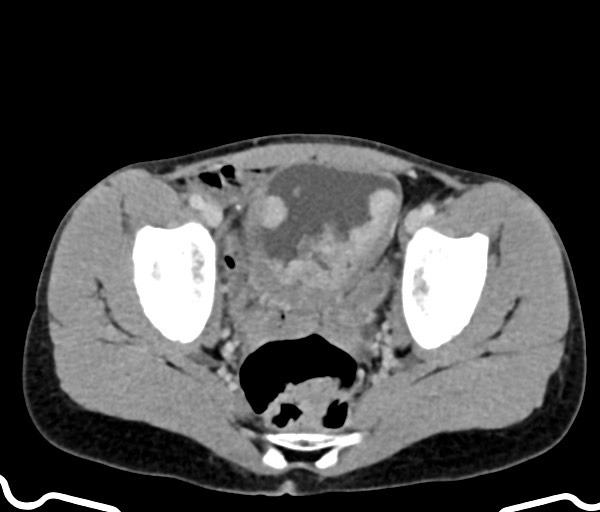

Q

weight loss

Gallbladder carcinoma is uncommon, with a poor prognosis. Five year survival is less than 5%.

It may present insidiously with weight loss or a palpable mass or with jaundice.

Case Discussion

Large distended gallbladder, which is entirely occupied by a solid internal mass, with internal haemorrhage.

Histopathology confirmed the radiological suspicion of a gallbladder carcinoma